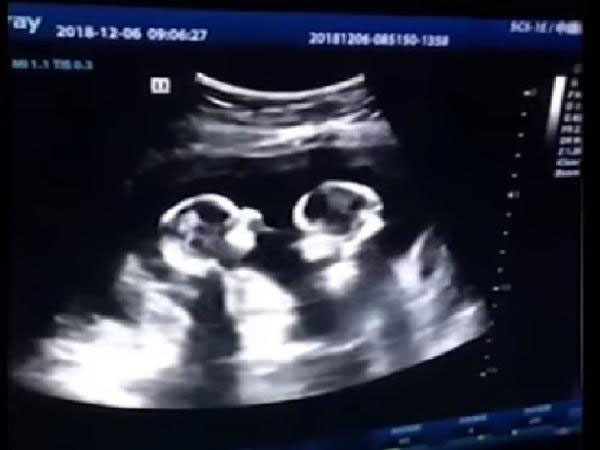

Một cặp song sinh vẫn ở trong bụng mẹ mà “chiến đấu” với nhau. Những hình ảnh này gây sốt trên cộng đồng mạng. Dù các bé chưa ra đời nhưng đã đủ "bản lĩnh" như này.

Mang thai song sinh có thể là tin tuyệt vời với nhiều người, nhưng liệu bao nhiêu người đã nhìn thấy các em bé như đang đánh nhau trong bụng mẹ. Nghe có vẻ khó tin đúng không, nhưng điều này đã xảy ra ở Trung Quốc.

Theo nguồn tin, đoạn video được lan truyền trên mạng xã hội Trung Quốc gần đây được ghi lại bởi người bố đang đưa vợ đi siêu âm. Người vợ đang mang thai 2 bé gái sinh đôi và đang ở tháng thứ 4 trong thai kỳ.

Hình ảnh siêu âm cho thấy 2 thai nhi dường như đang đá và va vào nhau liên tục. Kể từ thời điểm đăng trên Youtube, video được lan truyền rất mạnh mẽ.

Mr.Tao (28 tuổi), người bố của 2 bé gái này đã nói với trang Chinese News rằng anh cảm thấy rất thích thú với hành động của những đứa con chưa chào đời của mình. Anh còn hài hước nói rằng mình như đang xem một trận đấu quyền anh của 2 đứa con gái.

Video này ngay lập tức được chia sẻ chóng mặt trên các phương tiện truyền thông Trung Quốc. Tính tới thời điểm này video đã có hơn 2.5 triệu lượt xem và 80.000 bình luận trên mạng xã hội.